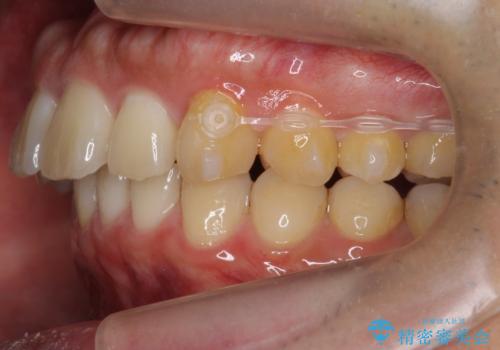

歯を抜かずに奥歯を後ろに動かすために、矯正用のミニスクリューを使用しています。

また、過蓋咬合(深いかみ合わせ)で食いしばりがきつく、歯の移動には大変時間がかかりました。

食いしばりがきついかたについては、長時間マウスピースをはめると奥歯が咬まずに前歯に負担がかかる場合があります。今回は使用時間を短くしたり、下の歯並びを早めにプレートタイプリテーナーに置き換えるような工夫を行い、治療を行いました。